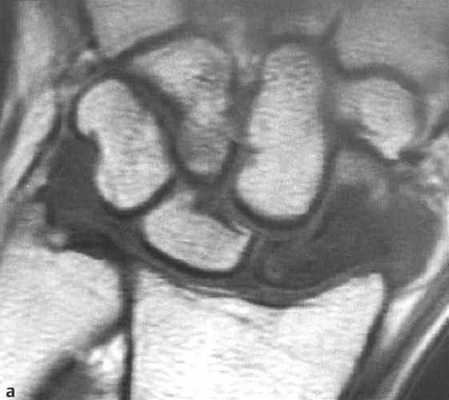

а, b Перелом ладьевидной кости (средняя треть), (а) Дополнительное наложение головчатой кости.

(b) Линия перелома лучше визуализируется при локтевом отведении и локтевом наклоне поверхности запястья.

а-d Перелом ладьевидной кости. МРТ. (а) Неконтрастное Т1-взвешенное изображение демонстрирует распространенные участки снижения интенсивности сигнала.

(b) Последовательность SТ1R демонстрирует гиперинтенсивный сигнал с гипоинтенсивной линией перелома.

(с) Т1 -взвешенное изображение после введения контрастного вещества. Проксимальная часть ладьевидной кости не накапливает контрастное вещество, что означает нарушение кровоснабжения и лишение жизнеспособности.

(d) Длительно существующий некроз ладьевидной кости с резорбцией проксимального фрагмента, дегенеративными изменениями, поражающими лучезапястный сустав с нестабильностью запястья и уменьшением высоты запястья.